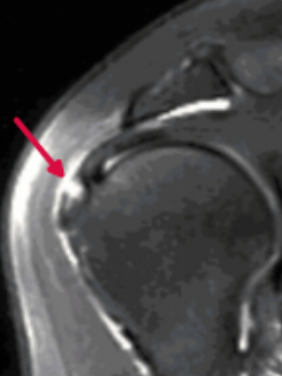

近日,即墨区中医医院接诊了一位53岁因车祸导致右肩外伤的男性患者,患者入院时伤肩疼痛、抬臂力弱,经磁共振检查为肩袖损伤(冈上肌肌腱损伤),后转入骨伤科为其行肩关节镜微创手术修复。

该患者的磁共振表现与损伤示意图如下(图中红色箭头所示肩袖损伤)